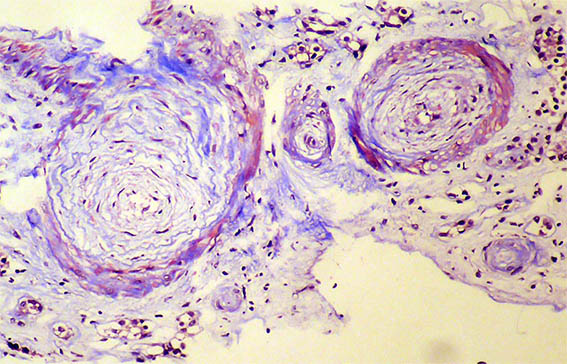

Se hace biopsia renal con impresión diagnóstica de lesión renal aguda. Ver las imágenes.

Figura 3.

H&E, X400.

Figura 4. H&E, X400.